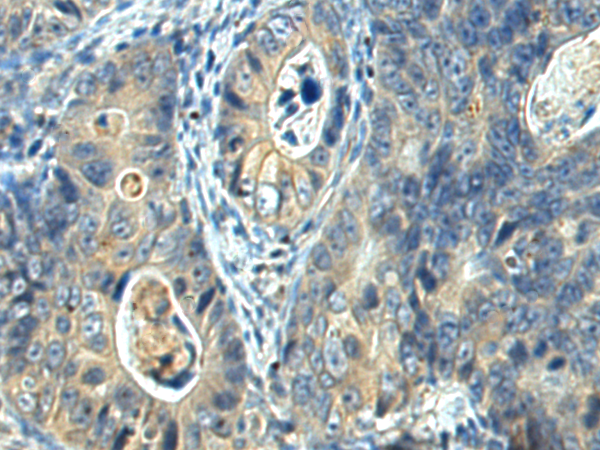

The image is immunohistochemistry of paraffin-embedded Human cervical cancer tissue using P11773(FUT1 Antibody) at dilution 1/35. (Original magnification: ×200) |